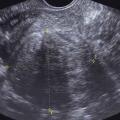

Échographie pelvienne (2D ou 3D)

Elle est toujours indiquée en cas d’hémorragie génitale d’origine haute, réalisée par voie sus-pubienne dans un premier temps, puis par voie endovaginale, vessie vide, dans un deuxième temps.Elle mesure la taille de l’utérus, qui est augmentée en cas d’adénomyose ou de fibrome.

Elle est utile à l’étude du myomètre, diagnostiquant fibromes (et leur cartographie) et adénomyose (fig. 2).

Elle permet le diagnostic des pathologies intra­cavitaires (telles que polypes endo-utérins et fibromes utérins), la mesure de l’épaisseur endométriale et apprécie la régularité de l’endomètre (cancer de l’endomètre).

Elle visualise les annexes et s’assure de la normalité de celles-ci.

Enfin, elle vérifie la présence ou non d’un épanchement dans le cul-de-sac de Douglas.

Le Doppler couleur couplé à l’échographie permet d’étudier la vascularisation de lésions organiques (pédicule de polype, fibrome).

L’hyperplasie de l’endomètre correspond à des anomalies structurales endométriales aux frontières de la bénignité et de la malignité. Le diagnostic est histologique. On retrouve à l’échographie un endomètre épaissi (fig. 7). L’hystéroscopie met en évidence un endomètre épais et permet de diriger les biopsies. La classification de l’Organisation mondiale de la santé (OMS) de 1994, reconduite en 2003, subdivisait les hyperplasies endométriales en quatre groupes : les hyperplasies simples sans atypies, les hyperplasies complexes sans atypies, les hyperplasies simples avec atypies et les hyperplasies complexes avec atypies. La classification de l’OMS de 2014, reconduite en 2020, a simplifié cette classification et conservé uniquement deux groupes : les hyperplasies endométriales sans atypies et les hyperplasies endométriales avec atypies/EIN (Endometrioid intraepithelial neoplasia). Il a été démontré qu’hyperplasie atypique et EIN étaient sensiblement synonymes.

Le cancer de l’endomètre est la première cause à évoquer en cas de métrorragies post-ménopausiques. Ces métrorragies sont spontanées, indolores et de faible abondance. Il s’agit en général d’un adénocarcinome. L’interrogatoire recherche des facteurs de risque généraux (âge, diabète, hypertension artérielle [HTA], obésité), locaux (irradiation pelvienne, hyperplasie adénomateuse ou atypique) ou hormonaux (puberté précoce, ménopause tardive, nulliparité, estrogénothérapie de traitement hormonal substitutif, prise de tamoxifène). L’examen retrouve un utérus modérément augmenté de taille. Le diagnostic repose sur l’histologie. On peut réaliser une biopsie d’endomètre en consultation à la pipelle de Cormier ou à la canule de Novak qui n’a de valeur que si elle est positive. Le prélèvement histologique peut aussi être réalisé par curetage bio­psique ou sous hystéroscopie, permettant la visualisation directe des lésions et le guidage des prélèvements histologiques par résection. L’échographie pelvienne recherche un épaississement de l’endomètre (mesure des deux feuillets supérieure à 4 mm) ainsi qu’une irrégularité de celui-ci, avec une mauvaise visualisation de l’interface endomètre-myomètre.